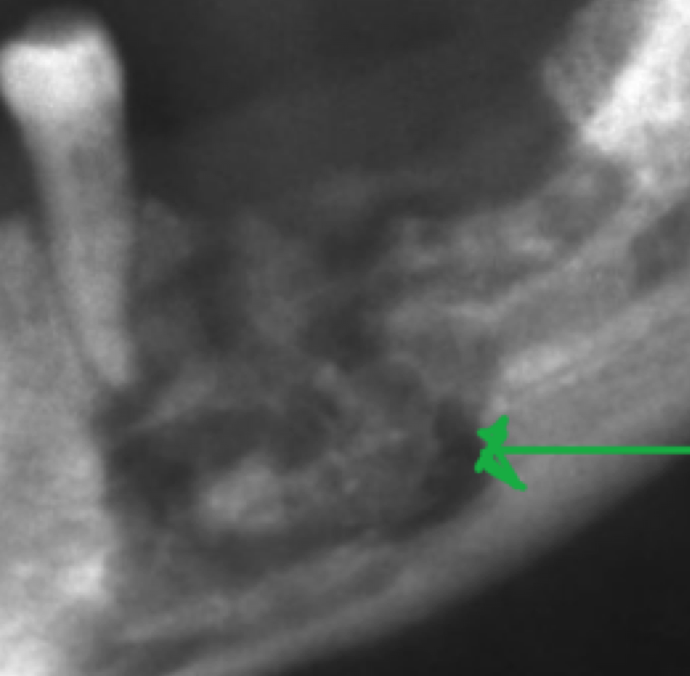

What does this radiograph show?

This shows osteomyelitis.

We can see the increased radiolucency (Uniform or patchy with a “moth-eaten appearance”)